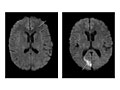

Magnetic resonance imaging (MRI) is a test that uses a magnetic field and pulses of radio wave energy to take pictures of the head. In many cases, MRI gives information that can't be seen on an X-ray, ultrasound, or computed tomography (CT) scan.

For an MRI of the head, you lie with your head inside a special machine (scanner) that has a strong magnet. The MRI can show tissue damage or disease, such as infection or inflammation, or a tumor, stroke, or seizure. Information from an MRI can be saved and stored on a computer for more study. Photographs or films of certain views can also be made.

In some cases, a dye (contrast material) may be used during the MRI to show pictures of structures more clearly. The dye may help show blood flow, look for some types of tumors, and show areas of inflammation.